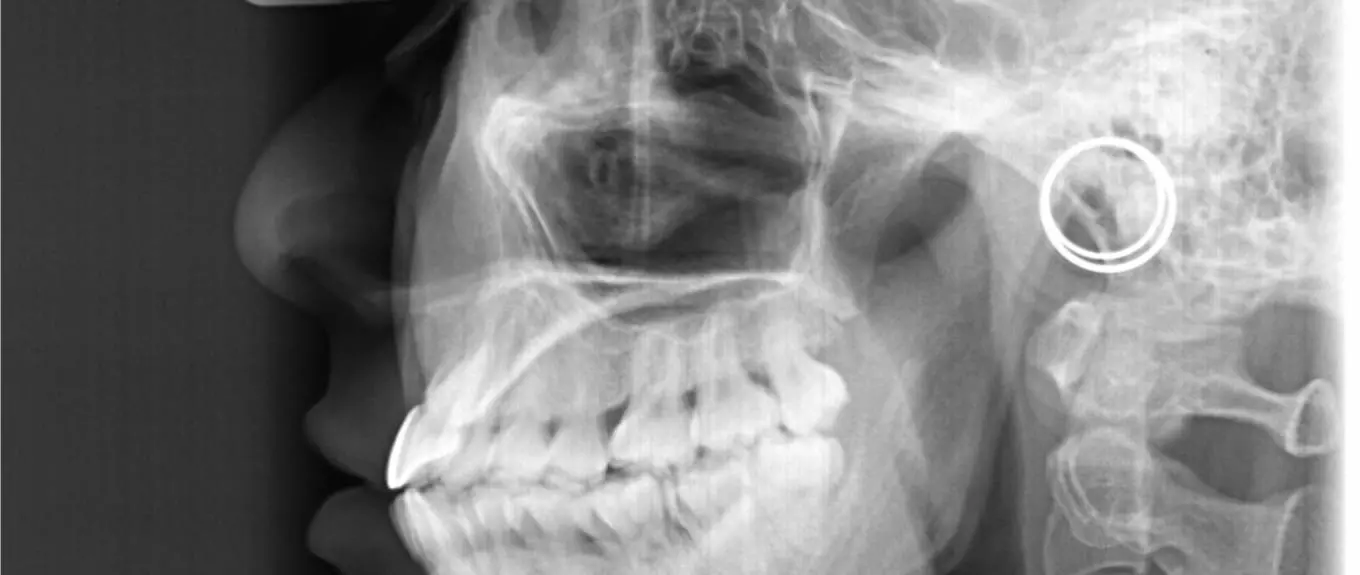

Of course, daily, most of us also use cephalometric radiographs to assist with our diagnosis and treatment planning. But how useful are cephalograms in routine practice? Do they provide us with critical insight that influences our diagnoses and treatment plans? Or are they unnecessary in some, most or indeed all of our cases? A team from Farmington, Connecticut did this neat study to answer these questions. The Angle Orthodontist published the paper.

They did an analytic study to assess the effect of the inclusion (or omission) of a lateral cephalogram as part of baseline records on both orthodontic diagnosis and treatment planning decisions.

They gave the raters the patients records. These were intra-oral and extra-oral photographs, digital models and a panoramic radiograph. They asked them to complete a 7-question survey concerning diagnosis and treatment planning for each patient. Six weeks later, they gave the raters the same records for the same patients. However, on this occasion, they included the lateral cephalogram.

All kappa values were high (ranging from moderate to near-perfect). This suggests that the inclusion (or omission) of a cephalogram had little effect on either diagnosis or planning.

In terms of treatment planning, the agreement concerning the need for extraction, expansion and orthognathic surgery all ranged from moderate to substantial. There was less agreement concerning the aetiology of malocclusion, which may reflect the inclusion of relatively mild cases.